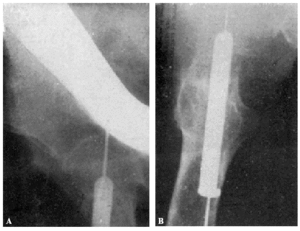

Fracaso número 2(observación número 2). F. S., setenta años4. Ingresa en el servicio con una fractura mediana del cuello femoral izquierdo. Osteosíntesis extraarticular (fig. 3. A y B). La impactación no ha resultado perfecta.

Figura 3. A: obs. núm. 2. El clavo no penetra suficientemente y la impactación, salvo en la parte superior de la línea de fractura, es muy defectuosa. B: obs. núm. 2. La posición del clavo es buena. C: obs. núm. 2. El clavo tiende a ser expulsado hacia fuera y apenas penetra en la cabeza femoral.

A los veinte días de la intervención pasa el enfermo a su domicilio, recomendándole que continúe en la cama. Pasado un mes vemos nuevamente al enfermo, el cual nos manifiesta que anda con mucha más dificultad que en los primeros días de permanecer en su domicilio, que fue cuando, por no haber interpretado bien nuestras indicaciones, comenzó a emprender la marcha. La radiografía (fig. 3. C) demuestra que el clavo apenas penetra en la cabeza femoral. A los ocho días hacemos otra radiografía (fig. 4. A), observándose que el trocáncer ha ascendido, a pesar de continuar guardando cama el enfermo. Ingresa nuevamente en el servicio, donde, con anestesia raquídea, retiramos el clavo, reduciendo las fracturas y volviendo a colocar un clavo más largo en buena dirección (fig. 4. B). Una radiografía practicada siete años y medio más tarde demuestra la no consolidación de la fractura, trastornos tróficos en cuello y cabeza femoral y que el cabo ha penetrado en el fondo de la cavidad cotiloidea, en donde ha labrado una cavidad (fig. 4. C).

Figura 4. A: obs. núm. 2. El trocánter ha ascendido francamente con relación a la radiografía anterior. El clavo tiende a salir de la cabeza por su parte superior. B: obs. núm. 2. Se extrajo el clavo y se colocó otro. El nuevo clavo está colocado en buena dirección, pero la reducción no es perfecta. C: obs. núm. 2. El clavo ha penetrado en el fondo de la cavidad cotiloidea, en cuyo lugar ha labrado una cavidad. Trastornos tróficos en cuello ycabeza femoral. El cuello del fémur ha desaparecido casi completamente.

En este caso el fracaso se debe a que la impactación no fue perfecta, y sobre todo, a haber el enfermo iniciado la deambulación al mes de intervenido, a pesar de que nosotros le ordenamos que guardara cama.